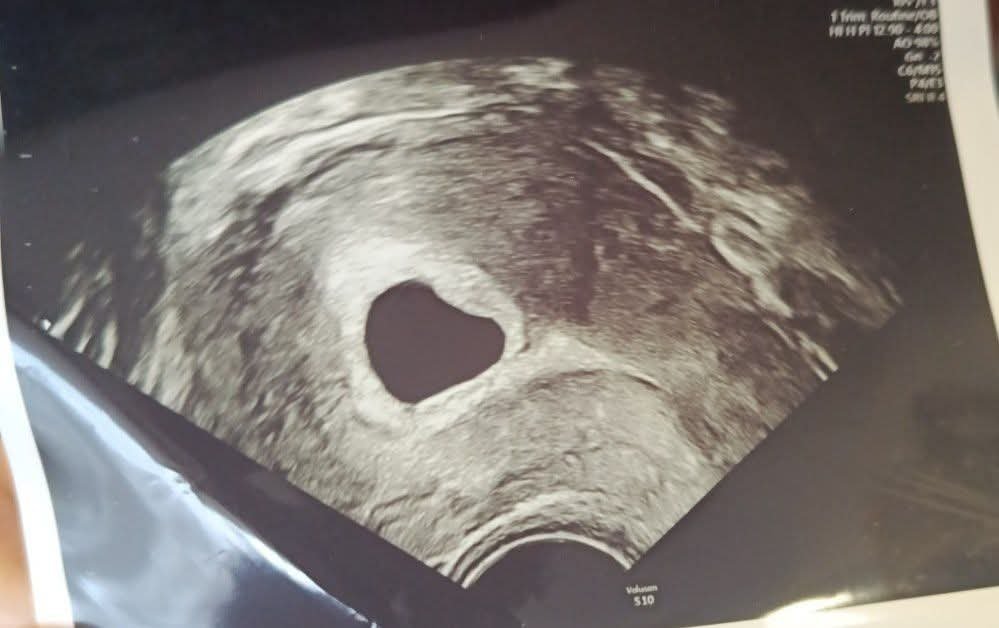

Знам че не е по темата,но все пак да попитам дали има някой който се е сблъсквал.

Според вас дали става въпрос за кухо яйце,снимката е направена в 6 г.с., но не се видя нищо друго освен един празен сак.Скоро ще ходя отново на преглед,но до тогава ще се побъркам.Ако някой се е сблъсквал с нещо такова ако може да каже Simple Smile

• Мнения: 272

Според мен е кухо яйце… съжалявам. Първата ми бременност беше такава и ми беше много тежко. Голям плоден сак и нищо в него. Според мен шансовете са почти нулеви да се промени картината… 6-та може би е рано да се прецени, но на мен този плоден сак ми изглежда прекалено голям. При мен го установиха в 9-та. Колко е голям сака?

Ами доктора тогава на прегледа нищо не ми каза но по самия начин на говорене на гледаме разбрах че не е както трябва.Но нито каза колко е голям сака нито на снимката е написано.

Ами виж първо какво ще стане на прегледа. Не трябваше да питаш… сега ще ти е още по-притеснено , а аз може би не трябваше да отговарям така. Просто наистина ми се струва прекалено голям. Иначе кухото ми яйце беше от инсемниция и просто спрях утрогестана и сама го изхвърлих. Не знам дали беше най-доброто решение… нямах проблеми и не съм имала силно кървене.. но зависи какво ще ти каже и доктора. Иначе 6та седмица е рано. Можа да се появи ембрионче. Просто, както казах - много голям ми се струва сака. Но ако ти кажа и колко невъзможни нещо са ми се случвали… Simple Smile така , че всичко е възможно. виж какво ще стане първо на прегледа.

Ооо не се притеснявай аз вече цяла седмица чета къде ли не какво ли не.Аз също мисля че сака е доста голям.Пък и това не ми е първа бременност.Колкото и скептично да изглежда не вярвам че ще се появи ембрионче предвид че сака е толкова голям и няма жълтично мехурче.Но утре ще стане ясно вече със сигурност